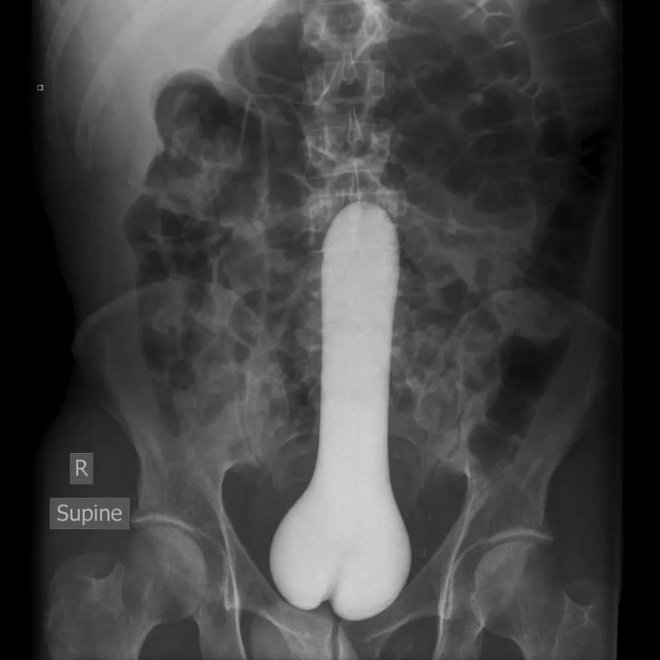

大型玩具

醫療診斷為「直腸異物」